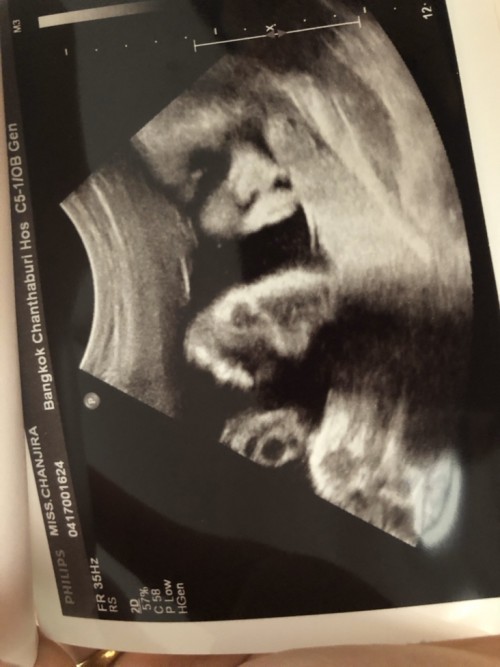

32+6แล้วจ้า ผู้ชาย 2100กรัม ปวดร้าวช่วงล่างมากจ้า